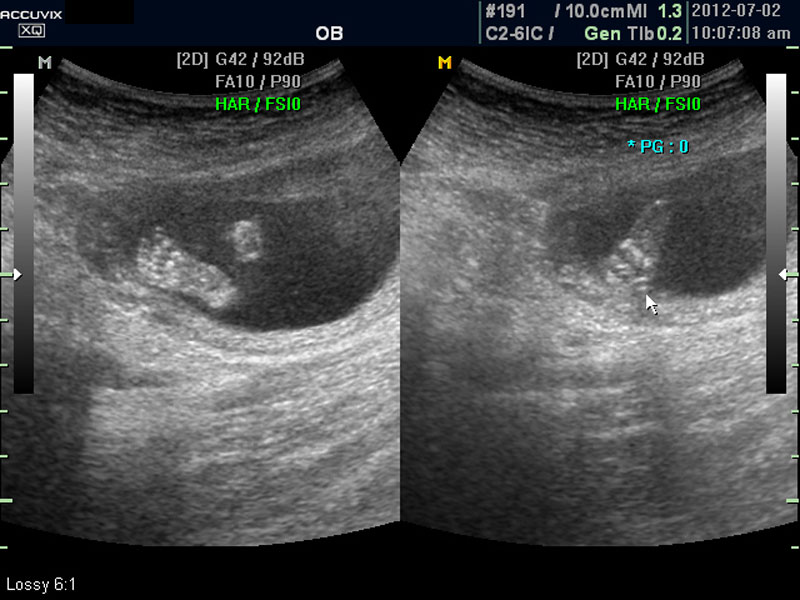

위 사진에서 빨간 동그라미로 표시한 부분이 태아의 머리를 위에서 내려다 본 수평 단면입니다.

하얗게 보이는 것은 뼈이고 내부에 검게 보이는 것은 뇌실에 고인 척수액 부분이며 내부의 하얀 부분은 뇌조직과 뇌실 내 맥락막이라고 하는 것입니다.

4. BPD

Biparietal Diameter의 약자로 머리를 위에서 보아서 양쪽 옆통수에서 반대쪽 옆통수까지의 길이입니다.

이는 임신 중기부터 후기까지 태아의 발육을 판단하는 중요한 지표이며 태아의 체중을 예측하는 데 쓰이는 지표 중 하나입니다.